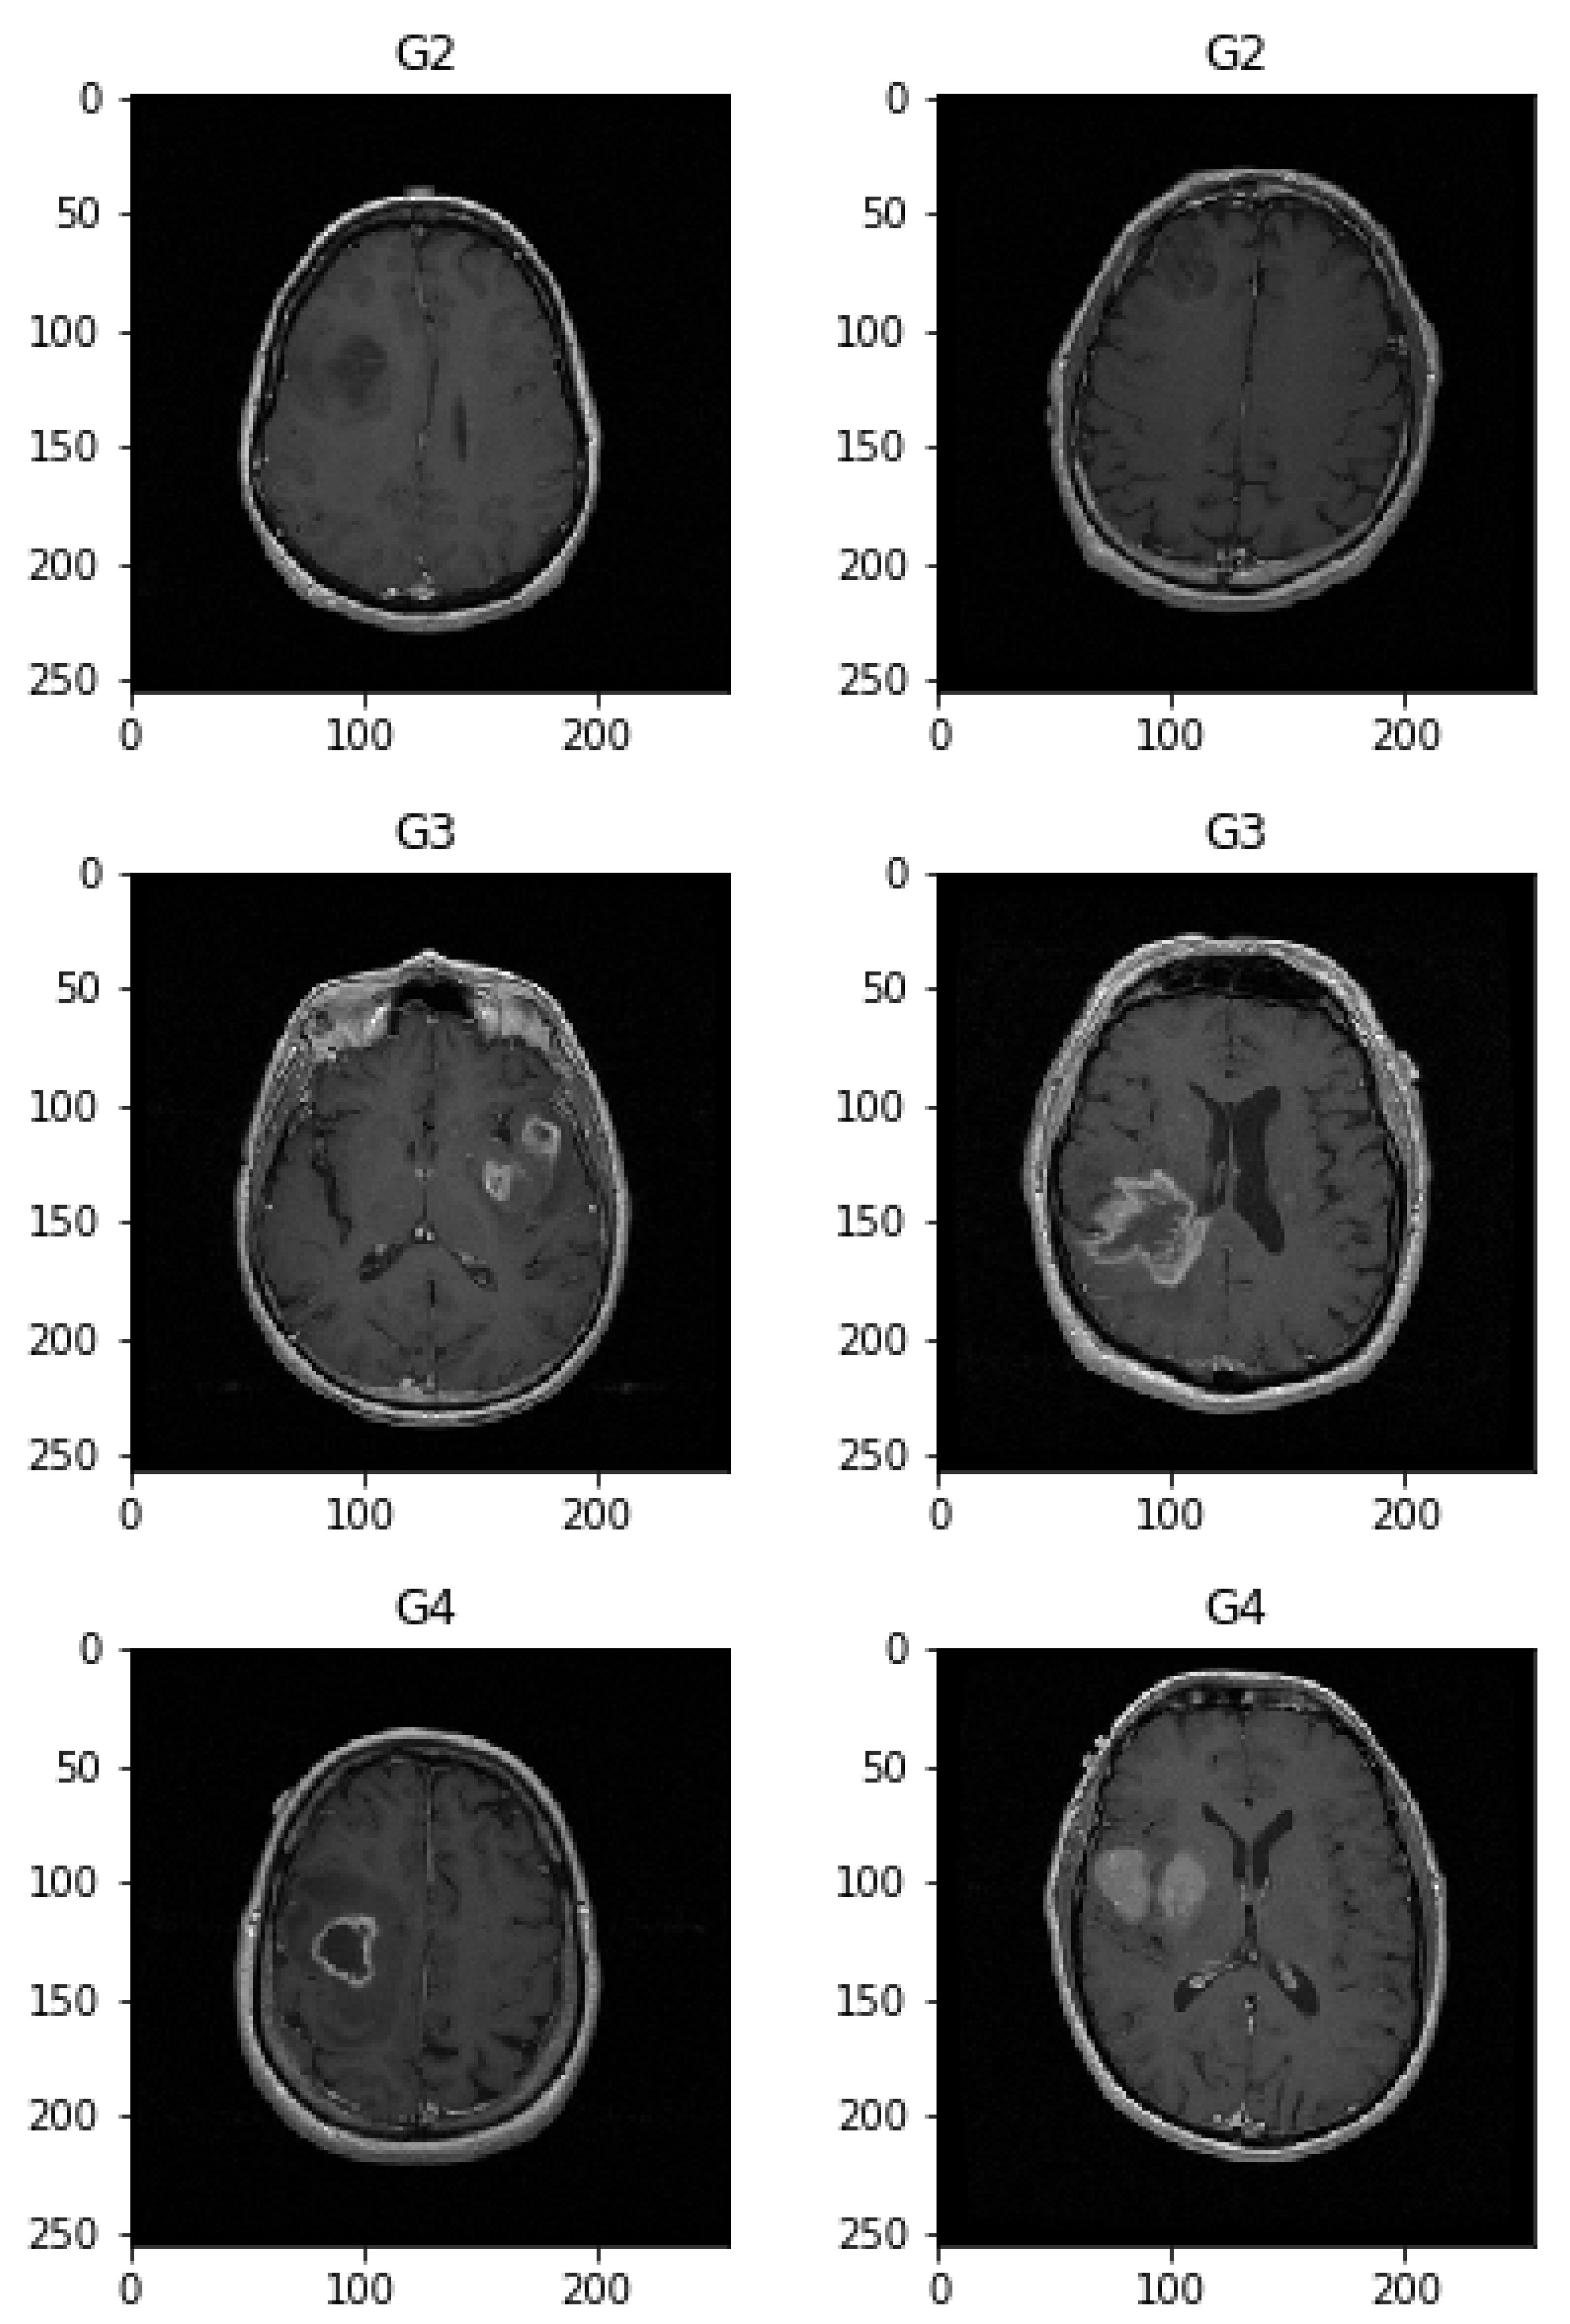

To help distinguish the tumor tissue and more precisely determine the tumor borders, the patients are typically injected with a contrast solution (Gadolinium). These images can be utilized in the classification of the tumor grade. Figure 4 shows axial MRIs with Gadolinium infusion of three grades of glioma brain tumors. Finally, Figure 5 shows three brain tumor cases from the second dataset utilized in this research [81]. As mentioned, all employed images were normalized to the [ 0 , 1 ] interval, and their dimension was set to 128 × 128 pixels.

Consequently, the first dataset size is increased to 16,000 and consists of 8000 healthy and 8000 glioma brain tumor images with grades I-IV. Out of 16,000, 2000 images, which include 500 images from each category (normal, grade II, III and IV) were used for testing, while the remaining are used for training. The second dataset initially consisted of a total of 3064 axial images split into three categories: 708 meningioma tumors, 1426 glioma tumors, and 930 pituitary tumors. After performing the same data augmentation process, each of the three categories consists of 1521 images utilized for training, and 115 used for the test, the grand total of 4908 images. More details regarding the pre-processing phase and the split datasets can be captured from [9,10].